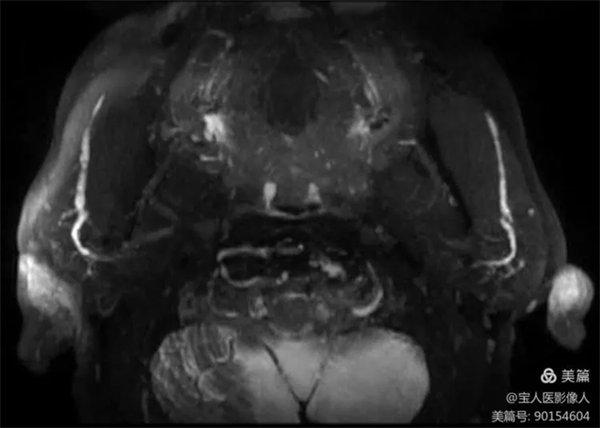

患者磁共振檢查,可清晰地顯示正常腮腺導管主干和大分支導管。

圖3,雙側腮腺導管主干及分支軸位圖像

醫學影像科副主任張軍暉醫生介紹,此圖像是在常規檢查中重建顯示腮腺導管主干及部分分支。如果行專門的腮腺導管磁共振成像技術,通過一些前期準備及掃描技術優化,成像效果會更好,結合強大的后處理技術,會更好的顯示腮腺導管及周圍組織結構。